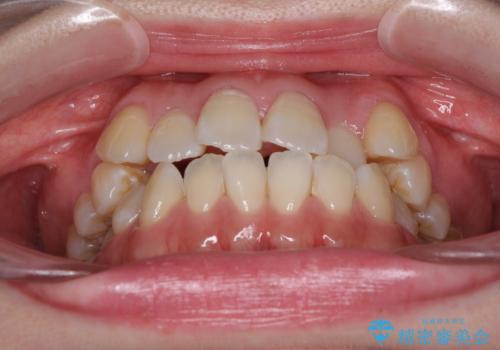

- 前歯がデコボコした上に口元が閉じにくいことを気にして来院された患者様です。

IPR(歯と歯の間を削る)と側方拡大では口の閉じにくさは改善できそうになく、一方で抜歯矯正を行うほどの突出感は認められませんでした。

親知らずを全て抜去し、歯列全体を後方に移動させることで口元の閉じにくさいを改善していくこととしました。